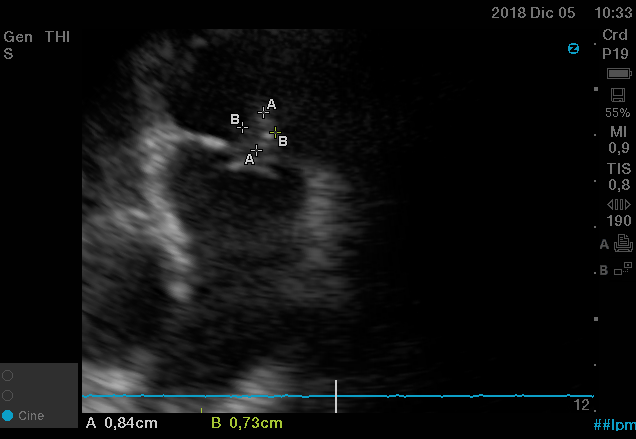

En diferentes escenarios clínicos para llegar a un diagnóstico precoz y administrar un tratamiento oportuno tales como: paro cardíaco, en anestesia, en patologías neurocríticas.

En nuestro afán por seguir el trabajo empezado hace ya varios años desde Europa (España) por impulsar la ecografía crítica para intensivistas, emergenciólogos, anestesistas, internistas, subespecialistas de obstetricia crítica, neumólogos y todo aquel médico interesado en aprender a utilizar la ecografía como parte de su examen físico, ahora desde Centroamérica (Panamá), hemos escrito el primer libro Latinoamericano-Europeo de ecografía crítica sub-especializado y dedicado exclusivamente al paciente con shock de cualquier etiología (obstructivo, distributivo, cardiogénico, hipovolémico) que involucra todas las modalidades ecográficas: ecocardiografía, ecografía pulmonar, vascular, abdominal, del sistema nervioso central/doppler transcraneal, etc) en el que participan muchos expertos en sus respectivas áreas tanto de Europa como de América y también algunos profesores del EDEC (Diploma Europeo de ecocardiografía / ESCIM- Sociedad Europea de Medicina intensiva).